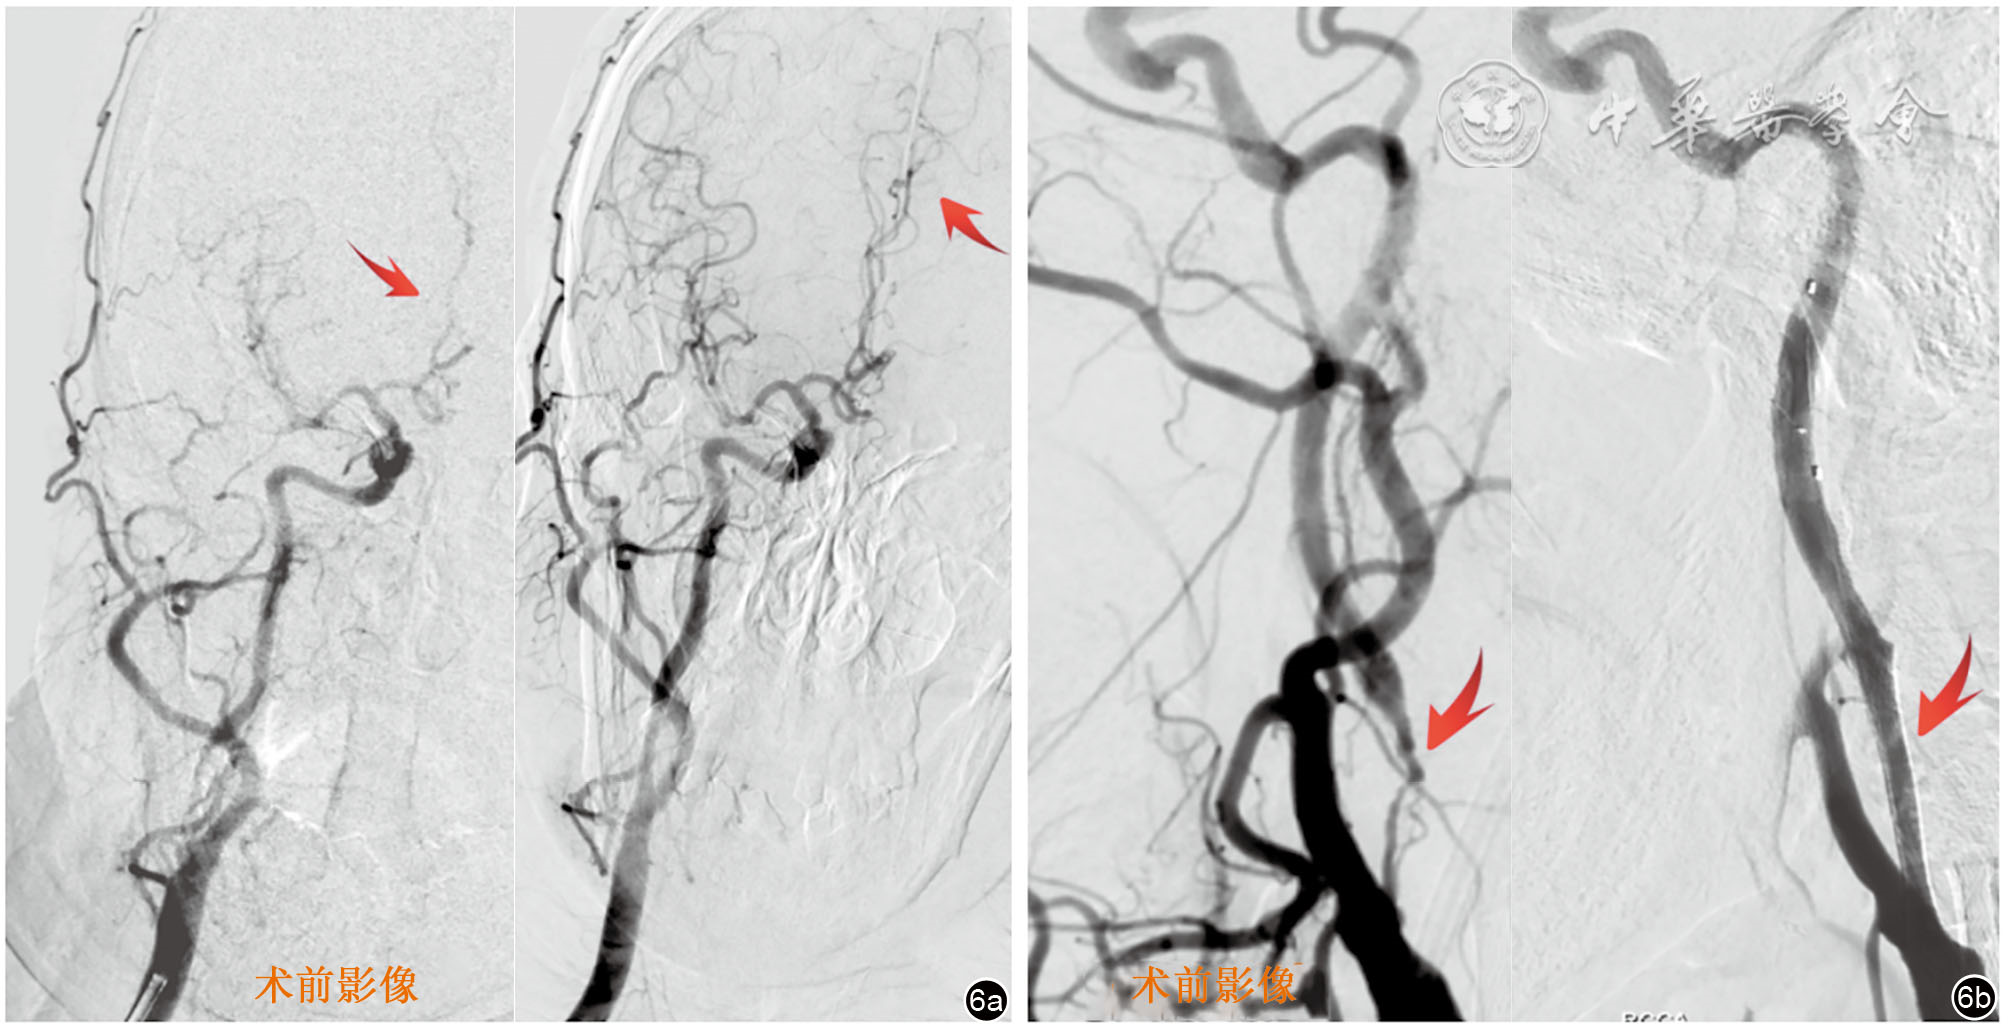

图6 患者分期行右侧颈动脉支架治疗数字减影血管造影影像。图a为正位的右侧前循环血管造影,对比术前及术后的大脑前对动脉,可见红色箭头所示前交通动脉开放,左侧额叶及胼胝体区血供改善;图b为侧位的右侧前循环血管造影,对比术前及术后可见极重度狭窄解除